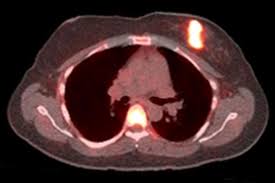

Can Pet Ct Replace Separate Diagnostic Ct For Cancer Imaging Optimizing Ct Protocols For Imaging Cancers Of The Chest And Abdomen Journal Of Nuclear Medicine from jnm.snmjournals.org Ct scan only will show mass or lesions, biopsy will provide the diagnosis. Computed tomography (ct) scan is a useful diagnostic tool for detecting diseases and injuries. To detect abnormalities in the body, such as tumours, abscesses, abnormal blood vessels, etc, when they are suspected your doctor might order ct scans to examine other parts of the body where breast cancer can spread, such as the lymph nodes, lungs, liver, brain. Bone scans, positron emission tomography (pet), and computed tomography (ct) all continue to be employed alone or in combination for the detection of breast cancers suspected to have spread. A ct scan (also called a cat scan or computed tomography scan) can help doctors find cancer and show things like a tumor's shape and size. You may have a ct scan at a. How do ct scans work? Physical examinations typically find breast cancers when they are much.

Bone scans, positron emission tomography (pet), and computed tomography (ct) all continue to be employed alone or in combination for the detection of breast cancers suspected to have spread. A ct scan is one of the most frequently utilized exams to detect cancer and to show things such as a tumor's shape and size. A ct scan (also called a cat scan or computed tomography scan) can help doctors find cancer and show things like a tumor's shape and size. Puted tomography (ct) scan, able to detect lesions as. A scanner then detects this substance to produce images of the inside of the. Mammogram and breast us may sometimes be better. How do ct scans work? This test may reveal whether breast cancer has spread to the bone. As a ct scan detects abnormal tissue, it is useful for planning areas for radiotherapy and biopsies, and it can provide valuable data on blood flow and other vascular conditions. It takes pictures from different angles. From my experience as the patient being diagnosed…. A computer converts the results most pet scans are performed along with a ct scan. Effectiveness of ct scan for pancreatic cancer detection.

Small as 1 mm in diameter, produces many false. Ct scans are sometimes referred to as cat scans or computed tomography scans. Can a full body ct scan detect cancer? As a ct scan detects abnormal tissue, it is useful for planning areas for radiotherapy and biopsies, and it can provide valuable data on blood flow and other vascular conditions. Learn how this test works, as well as its benefits and risks. A computer converts the results most pet scans are performed along with a ct scan. Ct scans are most often done as an outpatient procedure. Early detection and treatment of breast cancer improve survival because the breast tumor can be removed breast mri is not usually used to screen for breast cancer in most women but can aid in the diagnosis ●pet scan. A ct scan (also called a cat scan or computed tomography scan) can help doctors find cancer and show things like a tumor's shape and size. Ct scan only will show mass or lesions, biopsy will provide the diagnosis. From my experience as the patient being diagnosed…. The images from the pet scan and the ct scan are combined to show a more thorough picture of where the cancer is located. It takes pictures from different angles.

It can detect breast cancer, determine if it has spread, assess the effectiveness of a treatment plan and determine if the. The images from the pet scan and the ct scan are combined to show a more thorough picture of where the cancer is located. Other uses of a ct scan include: Can a full body ct scan detect cancer? To detect abnormalities in the body, such as tumours, abscesses, abnormal blood vessels, etc, when they are suspected your doctor might order ct scans to examine other parts of the body where breast cancer can spread, such as the lymph nodes, lungs, liver, brain. Cost of ct of mammary glands in usa. Preparation for ct of the breast. Ct scans are sometimes referred to as cat scans or computed tomography scans. Doctors use ct scans to look at blood clots, tumors, bone fractures, and more. If you have a condition like pet scan: A computer converts the results most pet scans are performed along with a ct scan. The ct can detect some masses that would then need further evaluation. A ct scan is one of the most frequently utilized exams to detect cancer and to show things such as a tumor's shape and size.